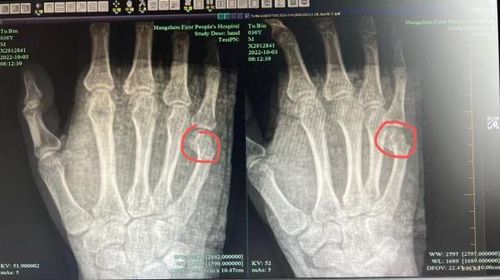

...吳爸爸右手掌腫脹、按壓時疼痛,X光檢查後顯示他第五掌骨骨折,骨頭出現明顯位移,需要住院治療。吳爸爸不...

...4A4A)** --- 醫師指出,李男右手第五掌骨頸骨折,斷端移位,評估後為其進行手法整復。醫師...

...動作,因此建議採用術後可盡早進行復健和活動的「微創掌骨鋼板復位內固定手術」,整個手術過程包含麻醉與恢...